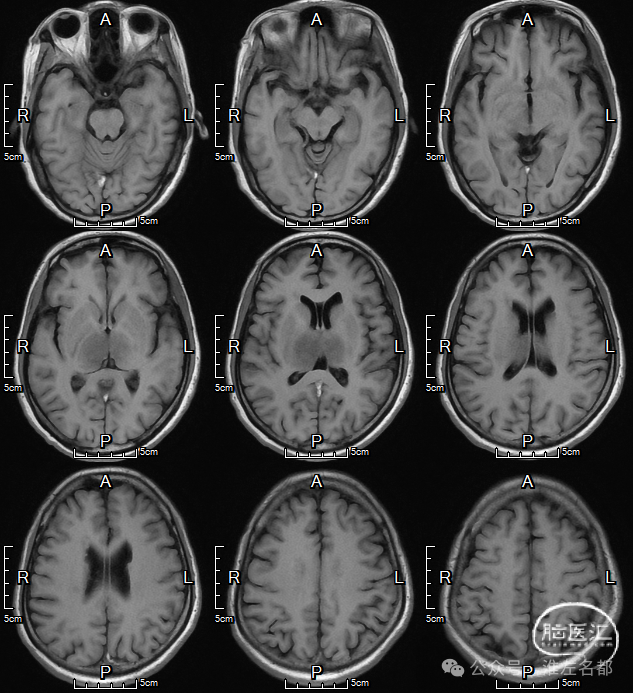

颅脑MRI

2024-9-25

T2

T1

FLAIR

DWI

双侧丘脑和右侧内囊-间脑淤血性梗死、水肿和伴渗血。